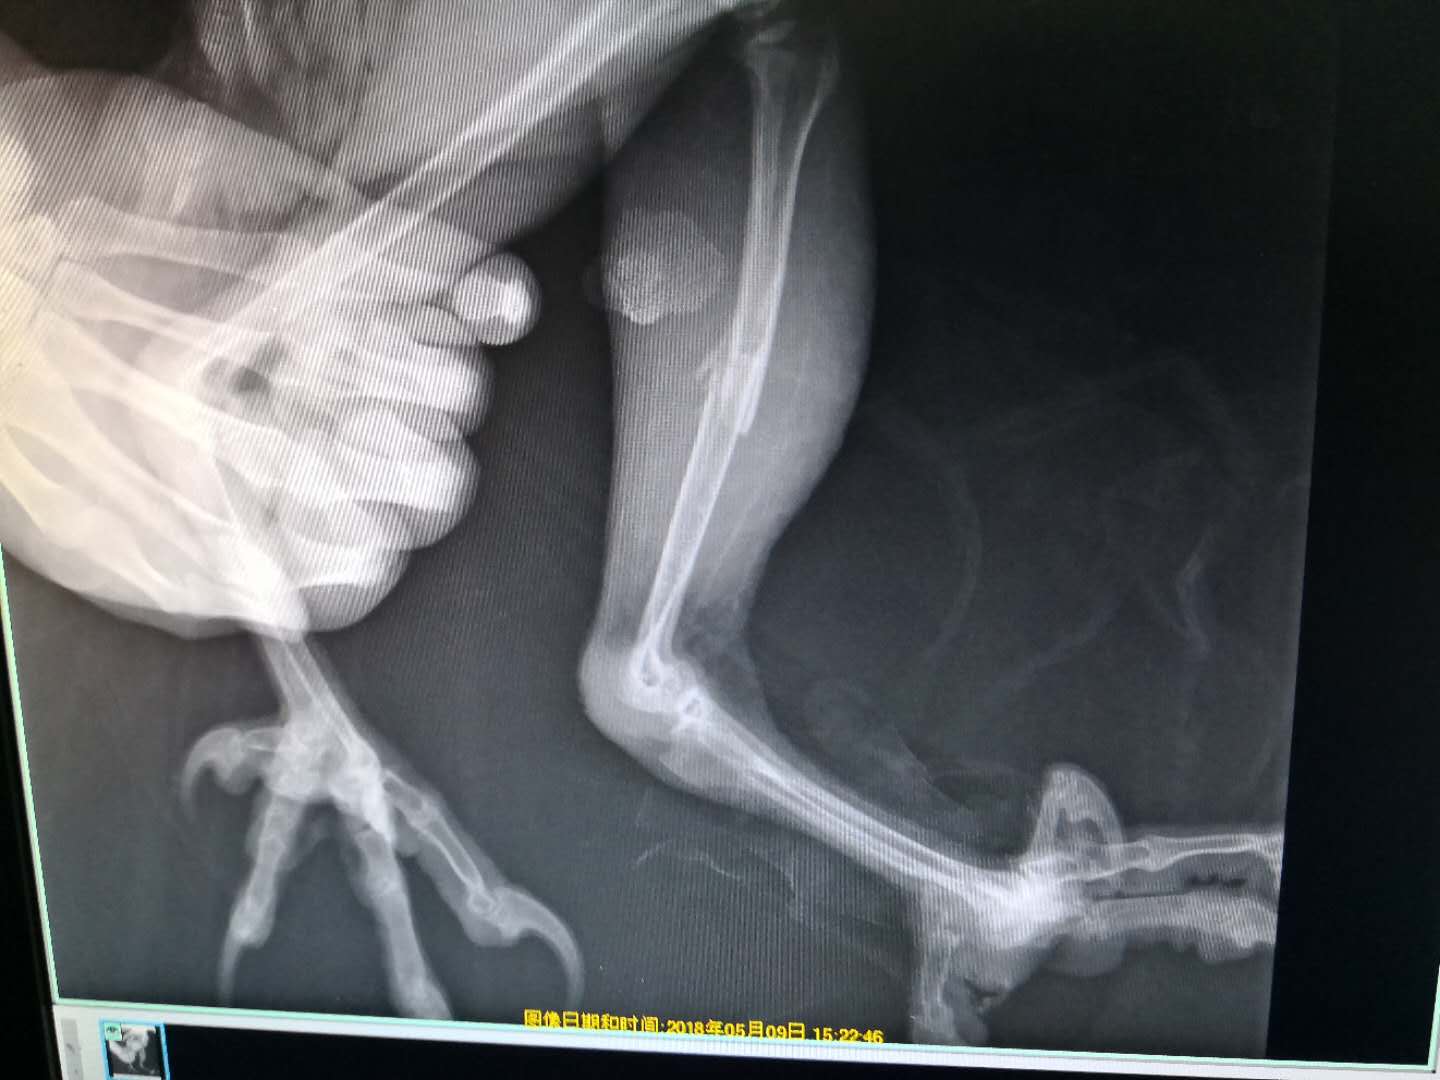

我在做手术​​​​​​​

手术很成功